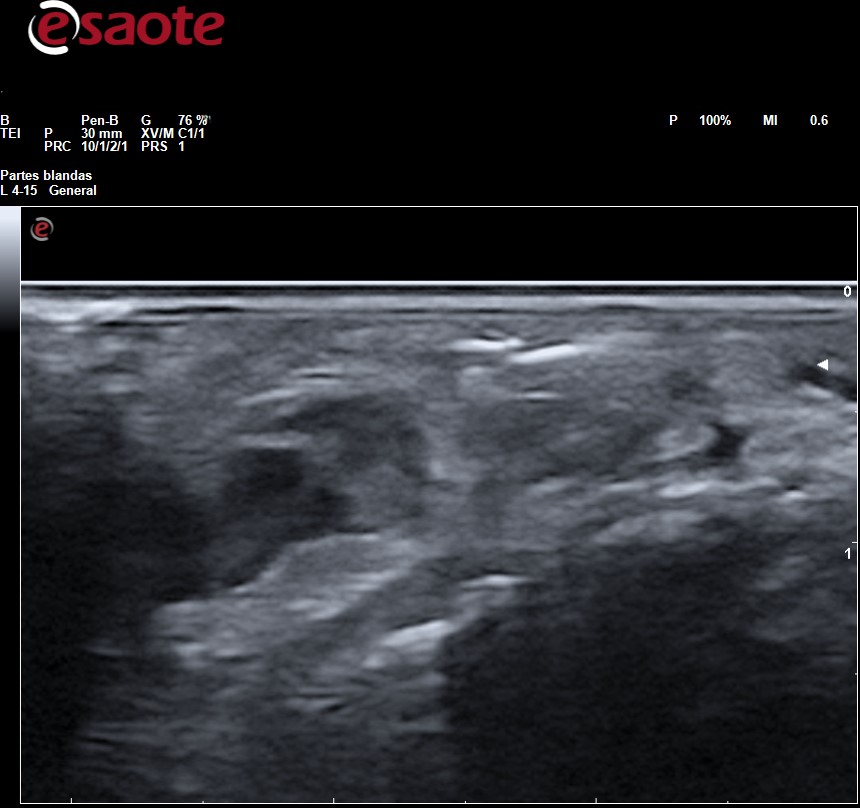

Observamos en el tejido celular subcutáneo imagen lineal hiperecogénica con artefacto de reverberación

La Rx es la primera técnica de diagnóstico para identificar y localizar cuerpos extraños, sin embargo, en ella solo pueden apreciarse la presencia de fragmentos radiopacos (metal, vidrio, piedra y algunos plásticos). Los fragmentos de madera, espinas de plantas y de pescados son indetectables. La Rx da una idea de la ubicación del fragmento y de sus relaciones con huesos y articulaciones adyacentes, pero no puede determinarse la ubicación del fragmento con relación a las estructuras adyacentes: tendones, vasos sanguíneos y nervios que sí podremos determinar con precisión mediante la ecografía lo cual facilita la planificación para su extirpación. Tanto los fragmentos radiopacos como los radiotransparentes se aprecian en ecografía como imagen hiperecogénica con artefacto de sombra acústica posterior o de reverberación según las características del cuerpo extraño rodeada de halo hipo-anecoico si hay granuloma.